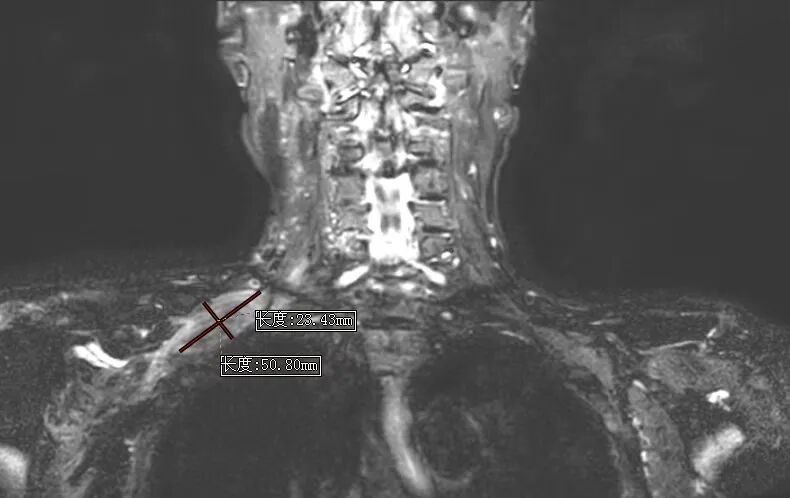

在史进主任的指导下,孙倩主治医师、胡雪婷住院医师详细询问病史、细致体格检查,凭借扎实的全科诊疗功底与严谨的临床思维,果断排除脑梗死及颈椎病变,高度怀疑为臂丛神经损伤,并及时为患者完善针对性臂丛神经磁共振检查。

检查结果证实了医师的判断:老人右侧臂丛神经被一巨大包块长期压迫,正是导致肢体麻木无力的“元凶”。明确病因后,全科医学科立即启动多学科协作,积极联系骨科专家、主任医师李波团队制定手术方案,顺利为老人手术解除神经压迫,从根源上解决了困扰他8个月的痛苦。